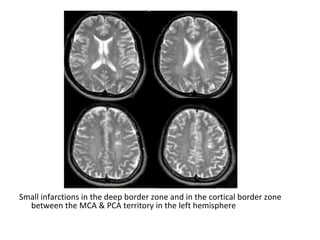

Small infarctions in the deep border zone and in the cortical border zone

between the MCA & PCA territory in the left hemisphere